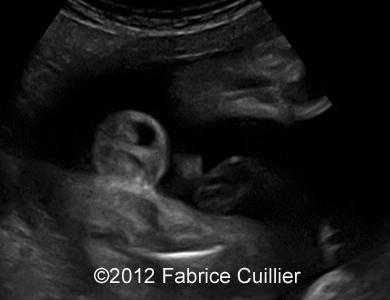

At 28 weeks, ultrasound examination revealed an abnormal fetus, with moderate polyhydramnios, moderate ileal and jejunal dilatation (Image 1) with normal peristalsis. There was no pyelectasy. There were no other dysmorphologic signs of aneuploidy. There was no sign of meconium peritonitis. There was no sign of congenital infection. The maternal serological status did not show any sign of maternal infection (TORCH and Parvovirus B19). Our first hypothesis of diagnosis was congenital chloride or sodium diarrhea. But sodium and chloride level in amniotic fluid were normal (results from first amniocentesis).

Image 1: At 28 weeks and 29 weeks, moderate ileal and jejunal dilatation.